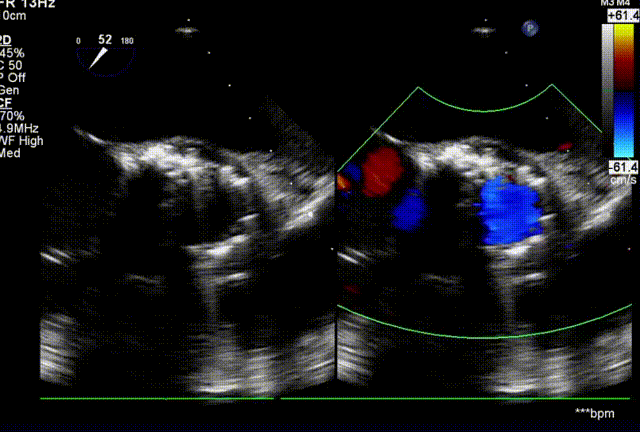

起搏150次/分,TaurusElite AV26瓣膜高位快速释放了四分之三,评估冠脉血流良好,无阻挡,瓣膜位置合适,释放后,造影显示反流增加,超声显示瓣周漏主要存在左右钙化嵴处,前向流速明显减小,跨瓣压差由术前60 mmHg减小到20mmHg,瓣膜横截面最大处18mm。

术后超声显示,瓣膜与主动脉贴合更好,但是在左右钙化嵴处还是存在少中量反流。

术后即刻超声评估

术中跨瓣压差为1mmHg,血流动力学得到明显改善。

术前压差

术后压差